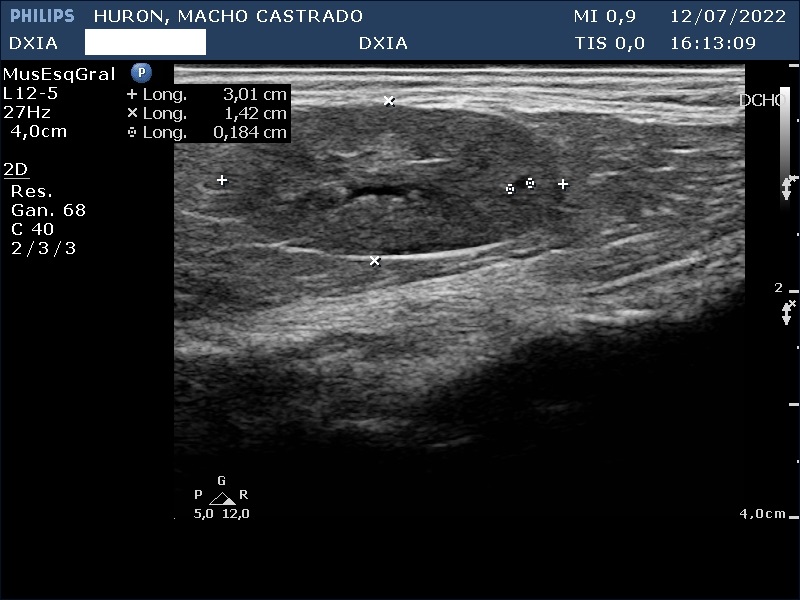

Estudio de ecografía abdominal

En esta ocasión os queremos presentar el caso de hurón (macho castrado) al que, debido a los síntomas que presentaba, tuvimos que realizarle un estudio ecográfico abdominal.

Presenta convulsiones así como hipoglucemias con picos de hiperglucemia por lo que su veterinario decide realizar un estudio de ecografía abdominal.

Hallazgos ecográficos